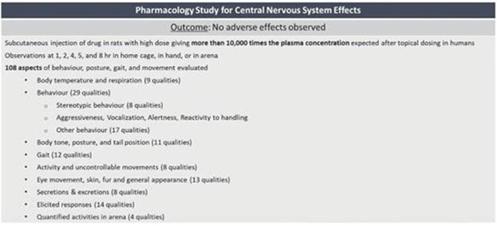

We have completed 20 safety pharmacology and toxicology studies to investigate the effects of CBN. We have also completed three Phase 1 safety and tolerability studies in healthy volunteers, two studies of which were conducted with varying concentrations of INM-755 cream and one study of which examined the non-CBN components of the cream base for INM-755.